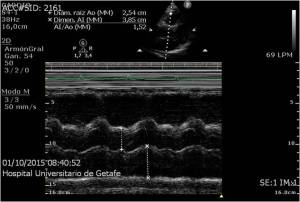

3.Modo M o de movimiento, se usa una representación gráfica de la señal a lo largo de la línea que representa el haz ultrasónico. Se observarán los ecos como puntos de brillo de distinta intensidad, siendo la distancia también proporcional al tiempo que tardan en ser recibidos. Esta línea de puntos es presentada en el monitor de forma continua a lo largo del tiempo.

Pueden seguir con precisión los movimientos de una estructura a lo largo del tiempo. Ecocardiografía.

Representación imagen Modo M.